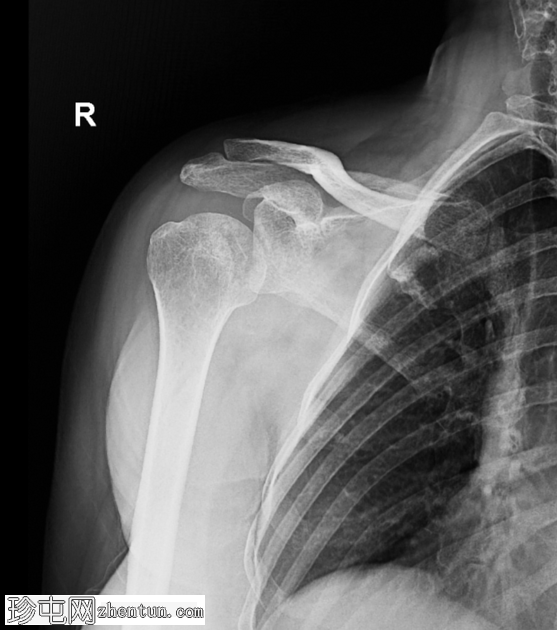

正位片

前后位片

肱骨头显示部分内旋。肩关节正常匹配度丧失。此位片未见明显相关骨折。

肩关节后脱位不常见,且在前后位X线片上常被忽略。

前后位片上的灯泡征提示肱骨头固定性内旋。

轴位片(或肩胛Y形位)对于确认后脱位至关重要。